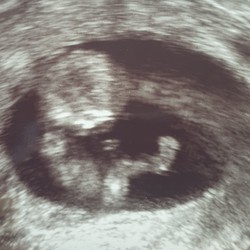

3e keer iui en 2-2-2021 uitgerekend vandaag een prachtig hartje gezien